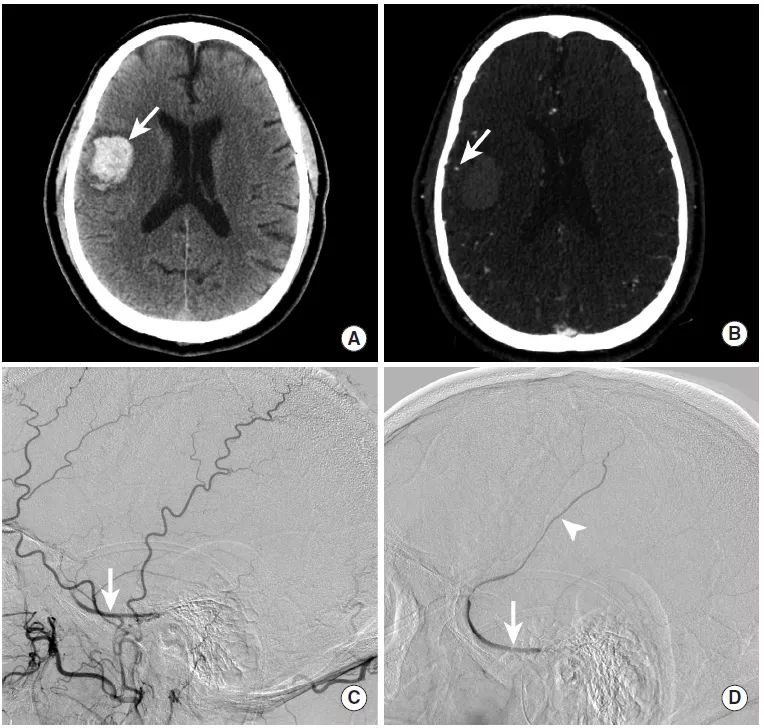

图14

本例为继发于硬脑膜动静脉瘘破裂的脑实质内出血。

图A:CT平扫显示右侧颞叶内高密度影,提示脑实质内出血(长尾箭头)。

图B:CTA显示出血区域边缘覆盖着皮层静脉(长尾箭头)。

图C:自右侧颈外动脉注射造影剂后,动脉期可见右蝶顶窦对比欠清晰(长尾箭头。

图D:DSA延迟期,右侧蝶顶窦(长尾箭头)和皮层静脉(三角箭头)造影剂进一步逆行填充。该皮层静脉对应于CTA上显示的静脉。